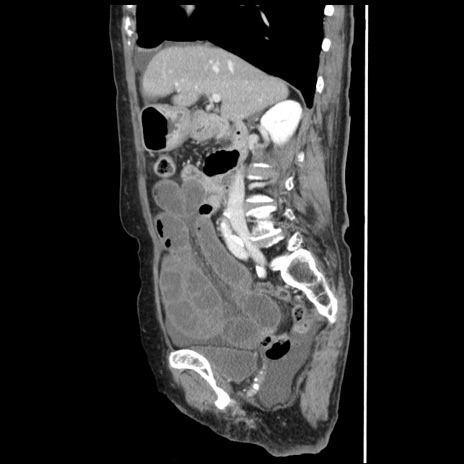

冠状断像

【症例】80歳代女性

【主訴】腹痛

【現病歴】8時間前から腹痛あり来院。

【既往歴】糖尿病、脂質異常症、子宮体癌にて子宮全摘術

【身体所見】意識清明・会話良好だが腹痛で苦悶様、全腹部にわたって反跳痛と圧痛あり

【データ】WBC 13600、CRP 0.14、LDH 224、CK 90